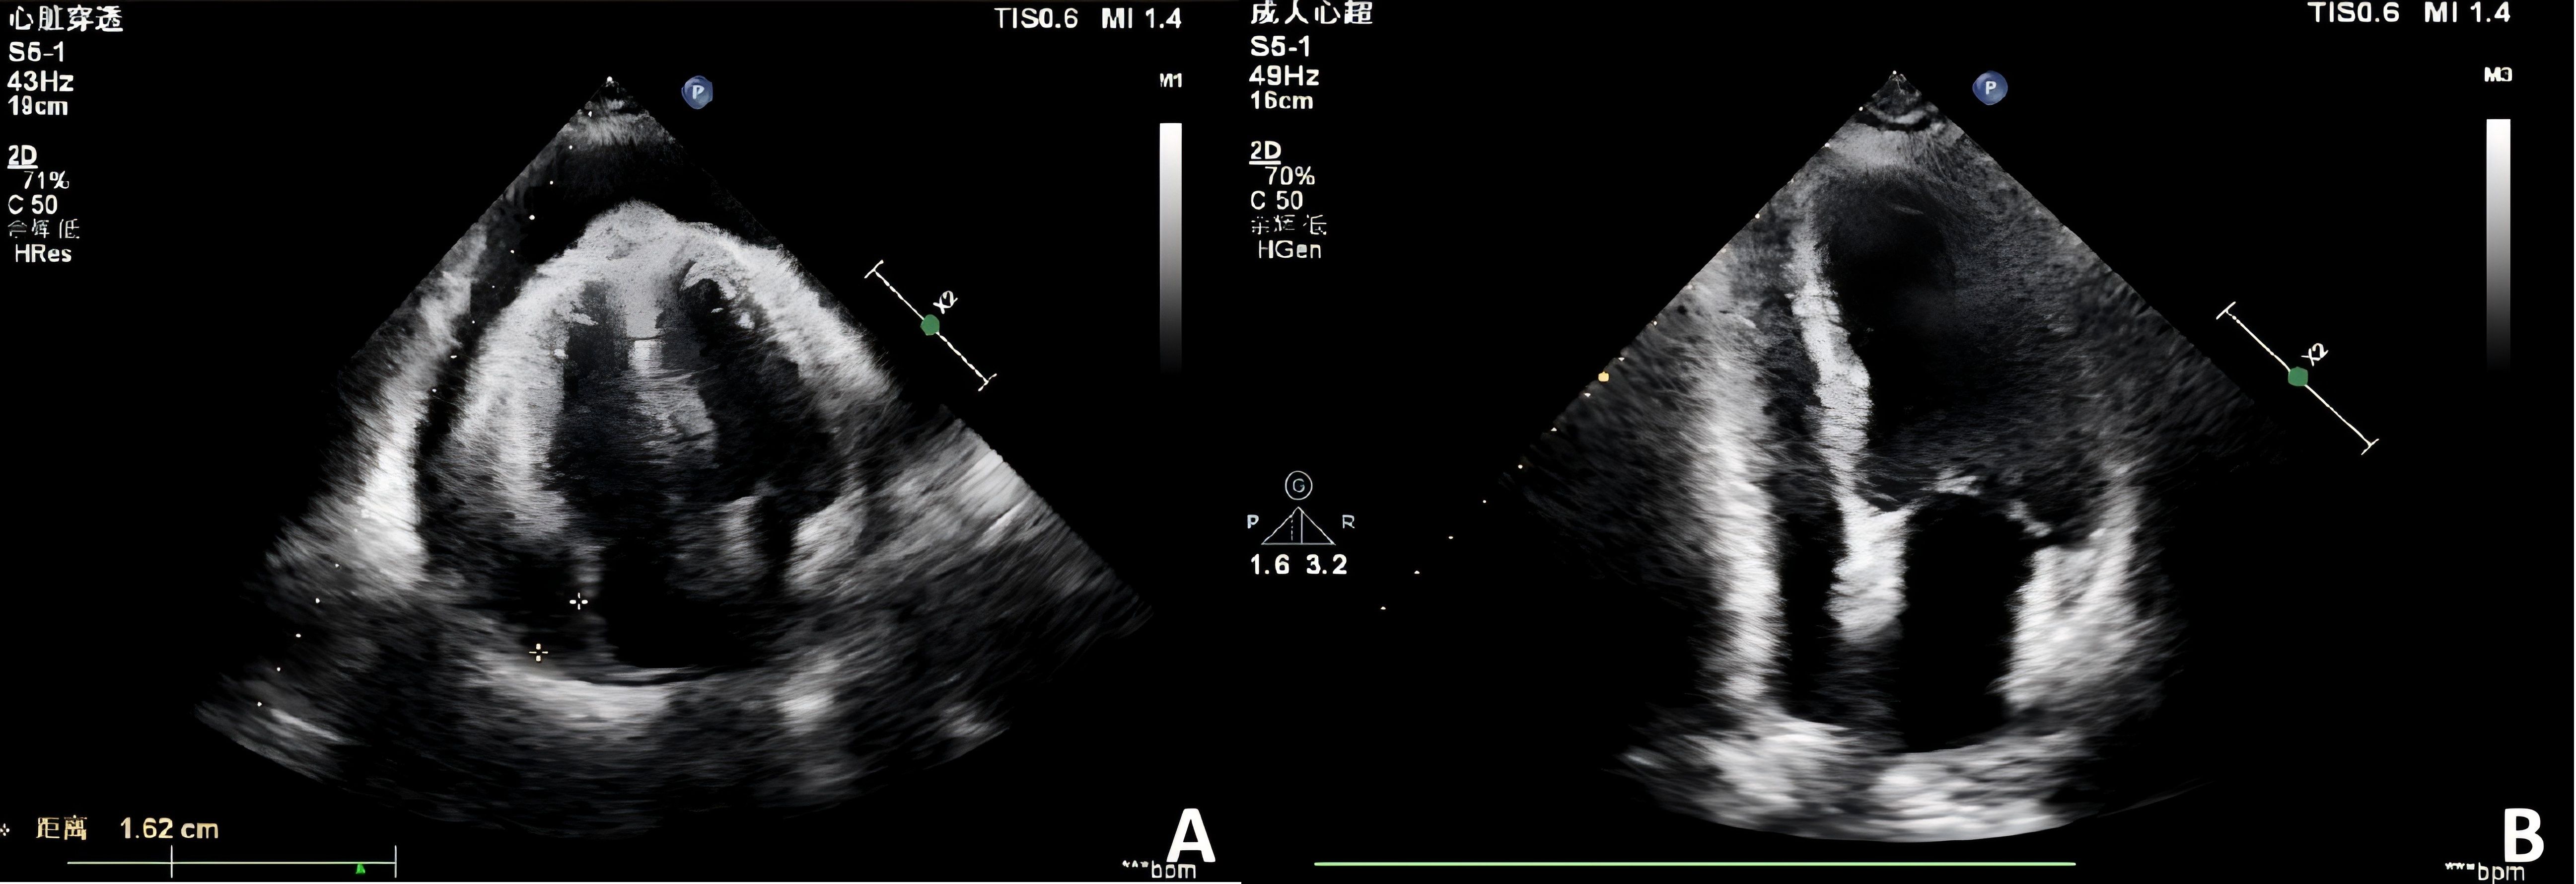

Fluid overload–associated large B-cell lymphoma (FO-LBCL) is a rare lymphoma that primarily involves serous body cavities (pleural, peritoneal, and pericardial spaces) without forming solid masses. Because FO-LBCL is uncommon, patients typically present with nonspecific symptoms—most frequently dyspnea from effusion—hindering early recognition and diagnosis. This study presents two cases of FO-LBCL and reviews the clinical characteristics, treatment regimens, and prognosis of 57 patients with FO-LBCL. Results showed that serous effusions involved the pleural cavity in 84.2% of cases, the pericardial cavity in 31.6%, and the peritoneal cavity in 21.1%. The most frequent presenting symptom was dyspnea (55.8%); other reported symptoms included chest tightness, gastric discomfort, fatigue, and lower-limb edema, reflecting respiratory, gastrointestinal, circulatory, and systemic involvement. Chemotherapy was the primary treatment (56.1%), most commonly the R-CHOP regimen. Univariate analysis identified the following factors as significantly associated with outcome: CD20 expression (P = 6 × 10-7), absence of CD138 expression (P = 0.0009), age > 65 years (P = 0.0015), LDH ≤500 U/L (P = 0.0064), presence of pleural effusion (P = 0.0099), CD79a expression (P = 0.0395), and use of rituximab-containing chemotherapy regimens (P = 0.0049). Our objectives are to characterize FO-LBCL comprehensively, clarify its differential diagnosis and management options, and address current gaps in clinical knowledge about this entity.